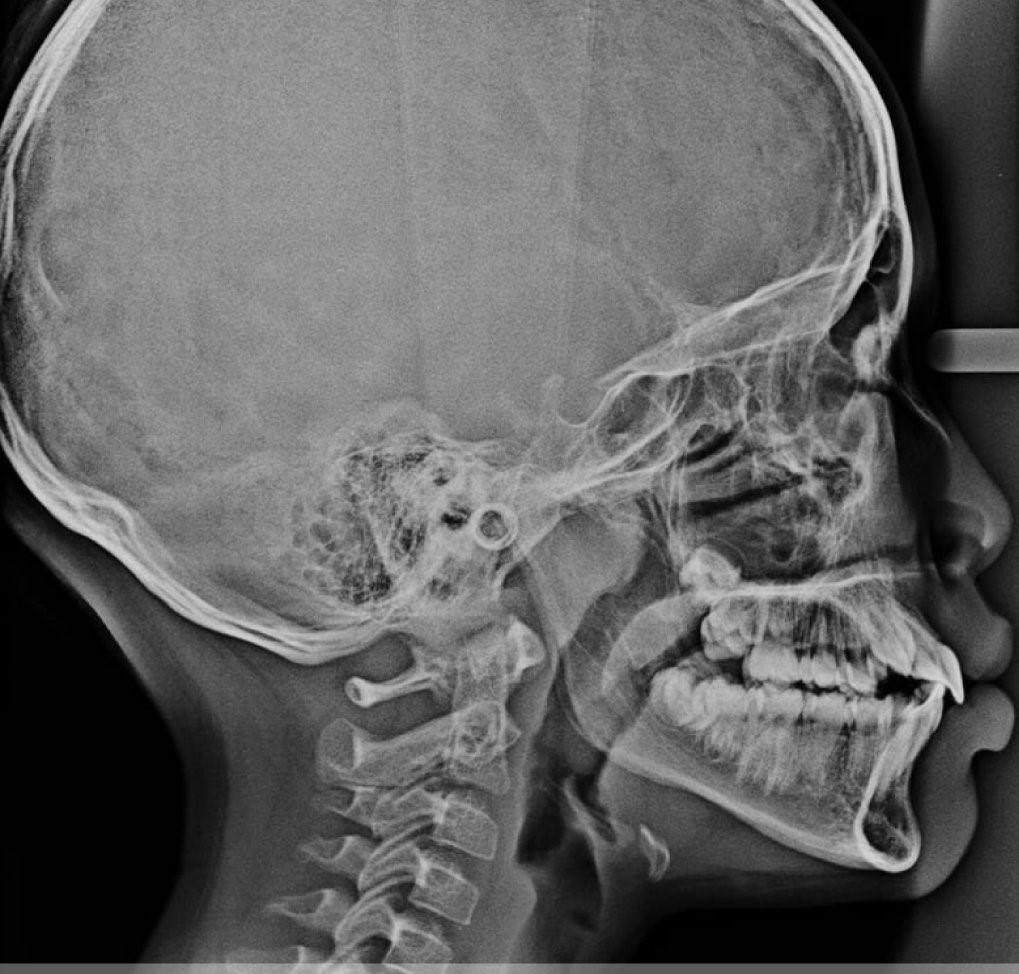

RONTGEN SEFALOMETRI

Sefalometri adalah jenis radiografi khusus yang digunakan untuk memeriksa struktur tulang wajah dan tengkorak, serta hubungan antar gigi, rahang, dan tulang wajah.

- Saat merencanakan perawatan ortodontik seperti pemasangan kawat gigi

- Untuk menganalisis hubungan antara tulang wajah dan gigi

- Ketika perlu memeriksa pertumbuhan dan perkembangan rahang pada anak-anak

- Saat mengevaluasi masalah maloklusi (gigitan yang tidak sejajar)

- Untuk memeriksa simetri wajah dan rahang sebelum prosedur pembedahan

- Ketika memerlukan evaluasi posisi dan kemiringan gigi sebelum perawatan ortodontik

- Untuk memonitor perubahan struktural selama perawatan ortodontik